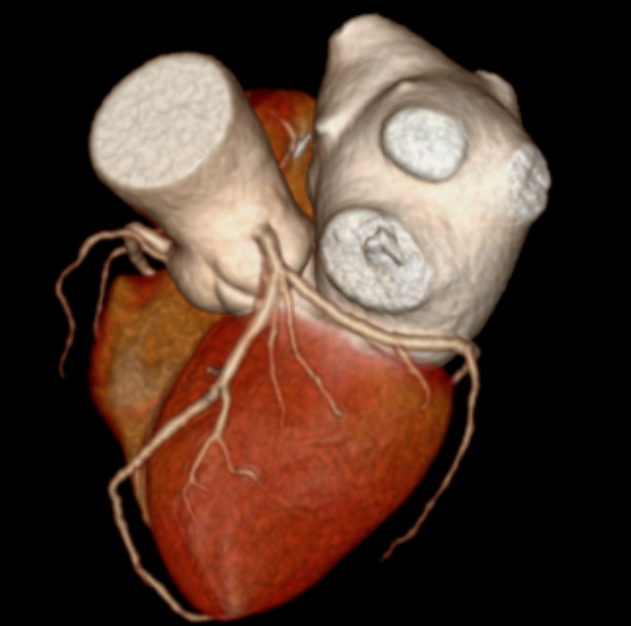

随即,张老先生被安排进行了一项关键检查:冠状动脉CT血管成像(CCTA)。对于一位81岁高龄、心律不齐且难以长时间屏气的老人来说,传统的CT扫描可能因呼吸运动和心跳产生伪影,导致图像模糊、诊断困难。然而,这次检查使用了——GE 256排宽体探测器CT。其核心优势在于“快”与“宽”:探测器覆盖范围宽,仅需0.3秒的极短扫描时间,就能完成心脏区域的完整数据采集。这意味着患者可以自由呼吸,无需刻意屏气,并且高速扫描能“冻结”心跳,极大削弱了心律不齐对图像质量的干扰,从而获得清晰、可靠的心脏血管图像。

CT表现:冠状动脉粥样硬化,左冠状动脉前降支近端中度狭窄,左冠状动脉前降支心肌桥形成。

冠状动脉CTA已成为筛查和诊断冠状动脉疾病的无创性“金标准”之一。它通过静脉注射对比剂,利用CT快速多层扫描和三维重建技术,直观展示冠状动脉的走行、管腔狭窄程度、斑块性质(如钙化斑块或软斑块)以及血管壁的情况。对于像张老先生这样的病例,CTA不仅能精准测量狭窄百分比,还能识别心肌桥这一解剖变异,评估其与狭窄的相互影响,为临床制定治疗方案(是药物保守治疗,还是需要介入支架或外科搭桥)提供了至关重要的参考。报告中提到的宽体探测器技术,代表了当前CT发展的前沿方向,特别适用于心率快、心律不齐、不能配合屏气或身体虚弱的患者,极大地拓宽了心脏CT检查的适用人群和诊断成功率。